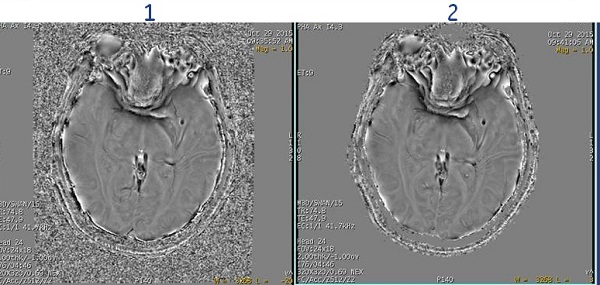

SWAN phase background removal

Use the SWAN phase background removal User CV with SWAN acquisitions. The signal dynamic range of SWAN Phase Images spans negative and positive values. Any automated or manual windowing thereby results in the background noise falling in the middle of the displayed dynamic range.This User CV allows automatic removal of background noise on phase images.

| 1 | Image acquired with SWAN phase background removal turned Off. |

| 2 | Image acquired with SWAN phase background removal turned On. |